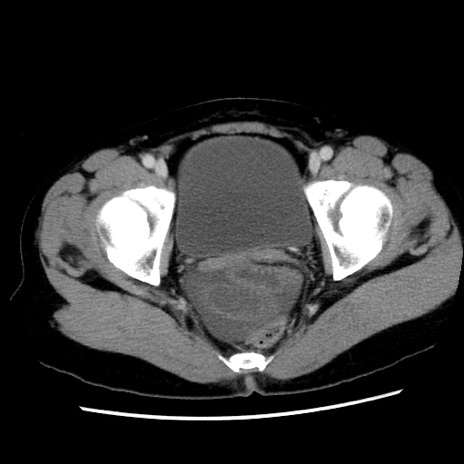

症例10(横断像)

【症例】 50歳代女性

【主訴】 腹痛

【現病歴】前日生レバーを食べた。今朝に排便あり。 昼前に突然発症の腹痛を生じ、当院救急外来を受診した。

【既往歴】 子宮筋腫にてで子宮全摘後

【身体所見】 意識清明、腹部:平坦、軟、下腹部やや左を中心に圧痛・反跳痛あり、筋性防御あり

【データ】WBC 7800、CRP 0.07